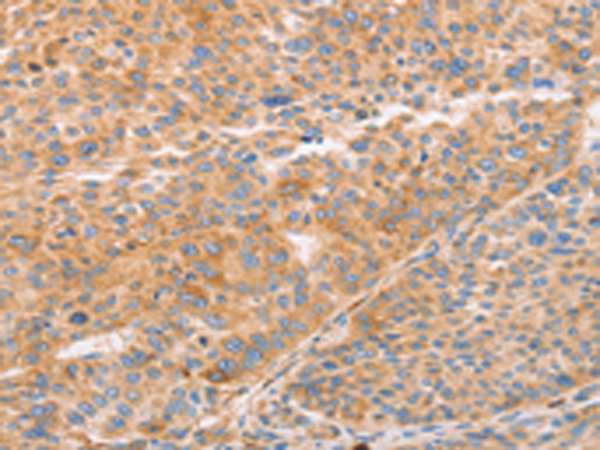

分类: 科研抗体货号: P11628别名: LEC; LMC; NCC4; CKb12; HCC-4; LCC-1; Mtn-1; NCC-4; SCYL4; ILINCK; SCYA16应用: WB,IHC反应种属: Human

分类: 科研抗体货号: P11664别名: CIB; CIBP; KIP1; PRKDCIP; SIP2-28应用: IHC反应种属: Human, Mouse, Rat

分类: 科研抗体货号: P11634别名: CD30; Ki-1; D1S166E应用: IHC反应种属: Human